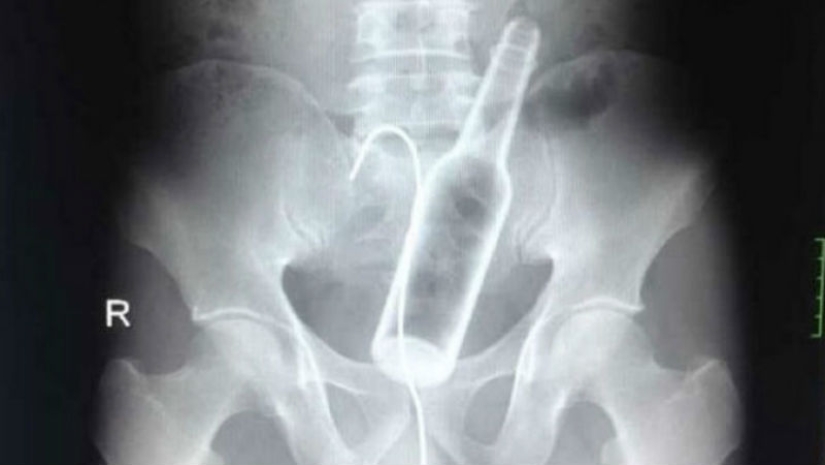

A man came to one of the Chinese hospitals with complaints of abdominal pain. Doctors took an X-ray and found a glass bottle in the stomach.